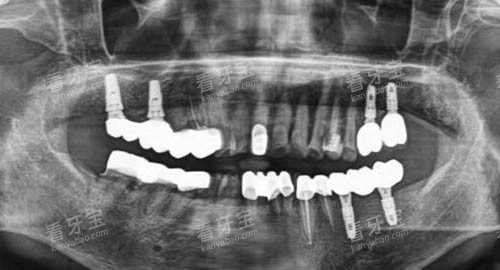

医院的医师墙展示了12位核心医师的履历,其中比较引人注目的是种植科管理者李代庆博士——这位留美归来的医师,曾完成浙江省首例穿颧穿翼高难度种植手术。

在他的带领下,团队创造了单日完成28颗种植牙的纪录。

智能化种植:像导航一样精密

采用瑞士ITI种植系统配合动态导航仪,医生能在术前通过3D模拟确定种植体位置,误差控制在0.1毫米以内。

种植牙:从经济型到奢华版全覆盖

韩国奥齿泰:1680元/颗(含基台+烤瓷冠)

德国ABT:5680元/颗(含全瓷冠)

瑞士ITI瑞锆亲水版:12800元/颗

我们不会推荐比较贵的,只会建议比较适合的。

了解师小周展示着价目表,比如这位阿姨牙槽骨条件好,选韩国种植体完全够用;但那位叔叔有重度牙周炎,就必须用亲水种植体。

4K显微镜:将牙体放大40倍,连根管内的细菌都清晰可见。

CBCT影像系统:360度扫描生成三维图像,避免传统X光的盲区。